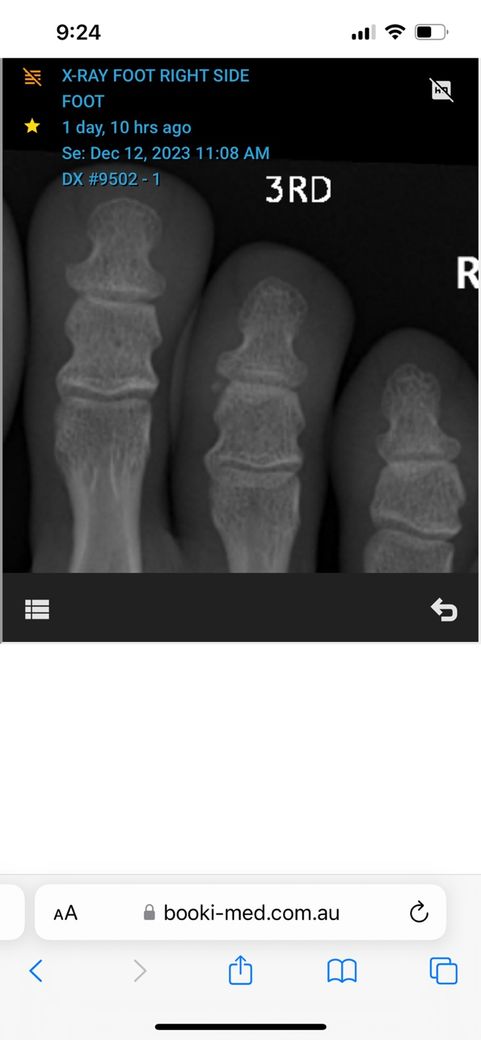

• 3번 째 사진

• 올리신 엑스레이 사진을 통해서 보았을 때에는 뼈의 골절 등 이상 소견이 보이지 않습니다. 다만 인대나 근육 등 부위에 대해서는 평가가 제한됩니다. 아무래도 추측건대 발레를 시작하고 발 부위에 충격이 반복되다 보니 충격으로 인한 조직 부종 및 염증 등이 생겼을 가능성이 높아 보입니다. 엑스레이 검사를 통해서는 보다 정밀한 소견들을 알 수 없습니다.